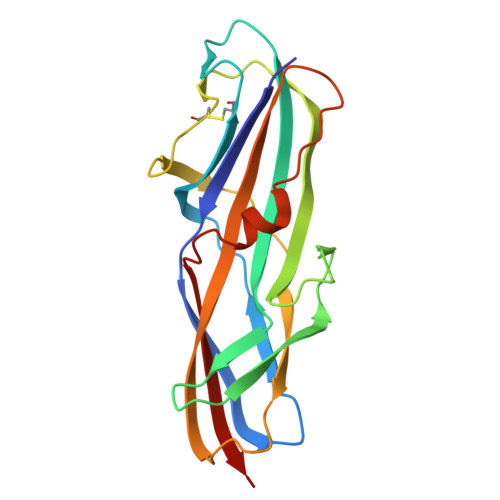

Carbohydrate-Lectin Interactions: An Unexpected Contribution to Affinity.

Navarra, G., Zihlmann, P., Jakob, R.P., Stangier, K., Preston, R.C., Rabbani, S., Smiesko, M., Wagner, B., Maier, T., Ernst, B.(2017) Chembiochem 18: 539-544

4Z3E, 4Z3F, 4Z3G, 4Z3H, 4Z3I, 4Z3J - PubMed Abstract:

Uropathogenic E. coli exploit PapG-II adhesin for infecting host cells of the kidney; the expression of PapG-II at the tip of bacterial pili correlates with the onset of pyelonephritis in humans, a potentially life-threatening condition. It was envisaged that blocking PapG-II (and thus bacterial adhesion) would provide a viable therapeutic alternative to conventional antibiotic treatment. In our search for potent PapG-II antagonists, we observed an increase in affinity when tetrasaccharide 1, the natural ligand of PapG-II in human kidneys, was elongated to hexasaccharide 2, even though the additional Siaα(2-3)Gal extension is not in direct contact with the lectin. ITC studies suggest that the increased affinity results from partial desolvation of nonbinding regions of the hexasaccharide; this is ultimately responsible for perturbation of the outer hydration layers. Our results are in agreement with previous observations and suggest a general mechanism for modulating carbohydrate-protein interactions based on nonbinding regions of the ligand.